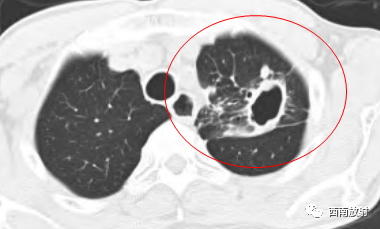

▲胞内分枝杆菌肺病,左肺上叶空洞。

▲胞内分枝杆菌肺病,小叶中心结节(树芽征)

▲胞内分枝杆菌肺病,小叶中心结节(树芽征),双肺多发厚壁空洞。